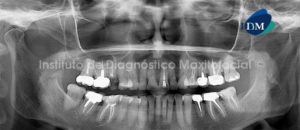

Paciente de sexo femenino y de 59 años de edad es referida al Instituto de Diagnóstico Maxilofacial para realizar el estudio de evaluación ósea para la colocación de implantes, lo cual llamo nuestra atención la presencia de un hallazgo radiográfico en el maxilar inferior.